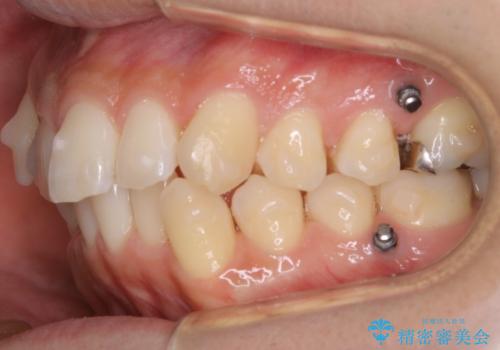

ガタつき自体は歯列の幅の拡大やディスキング(IPR)でほとんど解消可能でしたが、噛み合わせのズレは歯の移動が必要だったため、左上にマイクロインプラントを使用し噛み合わせの改善とガタつきの解消を同時に進めるという方針をとりました。